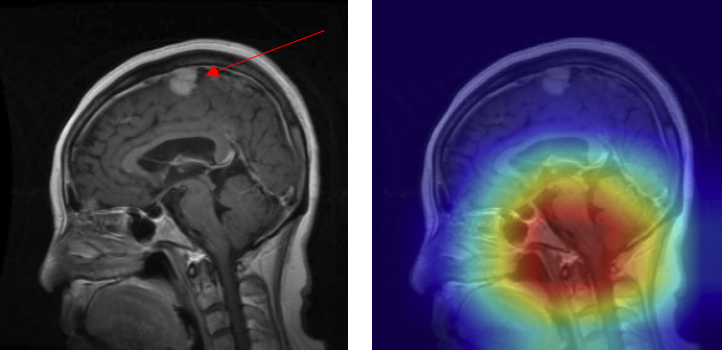

• Mislocalized attention - In some cases, the model predicted the presence of a tumor but focused on the wrong anatomical region. For example, a meningioma at the top of the brain (arrow) was misclassified as a pituitary adenoma because the Grad-CAM highlighted the sellar region instead of the true lesion (Figure 16).

• Figure 16: Mislocalized attention — meningioma (true) misclassified as pituitary adenoma with 0.99 confidence: (A) original with arrow marking lesion, (B) Grad-CAM focusing incorrectly on the sellar region.

Mislocalized Attention Example

These misclassifications demonstrate that although the model achieves strong overall performance, it can still base predictions on spurious cues (edges, background, or unrelated anatomy) rather than the lesion itself. Addressing these failure modes will require improved preprocessing (e.g., skull-stripping, intensity normalization), data augmentation strategies to disrupt shortcut reliance, and post-hoc calibration to temper overconfident errors. For clinical translation, such measures are crucial to ensure that model focus consistently aligns with the pathology, thereby supporting safe and trustworthy decision support in diagnostic settings.